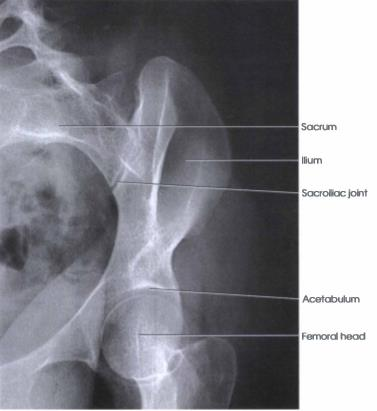

ILIUM PROJECTIONS

1. AP OBLIQUE PROJECTION

2. PA OBLIQUE PROJECTION

AP OBLIQUE PROJECTION

PP: Supine; RPO/LPO; unaffected side elevated 40o (places broad surface of the wing of affected ilium // to IR); shoulder, hip & knee elevated

RP: Level of ASIS

CR: ┴

SS:

• Unobstructed projection of ala & sciatic notches

• Profile image of acetabulum

• Broad surface of the iliac wing without rotation

PA OBLIQUE PROJECTION

PP: Prone; RAO/LAO; unaffected side elevated 40o (places affected ilium ┴ to IR); patient rested on forearm; knee of elevated side flexed

SS: Ilium in profile

• Femoral head within acetabulum